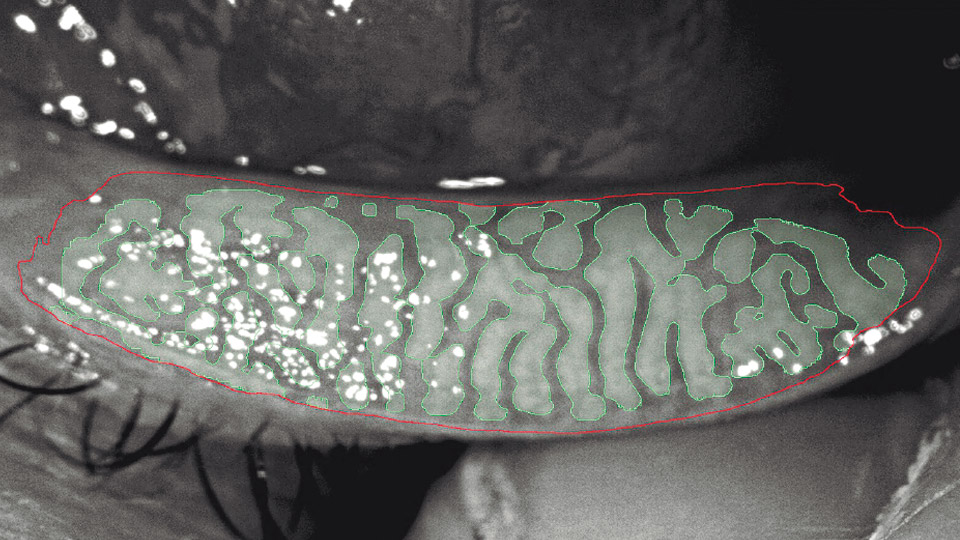

La meibografía es una prueba de imagen no invasiva diseñada para visualizar de forma precisa las glándulas de Meibomio, estructuras situadas en los párpados superiores e inferiores. Estas glándulas producen la capa lipídica de la lágrima, esencial para evitar su evaporación rápida y mantener la superficie ocular estable. Cuando se alteran, disminuye la calidad lagrimal y aparecen molestias que pueden confundirse con fatiga visual o alergias. La meibografía permite ver directamente si estas glándulas están sanas, acortadas, dilatadas o ausentes, aportando información que antes solo podía sospecharse.

La realización del estudio es sencilla, rápida y completamente indolora. El paciente se sienta frente a un equipo dotado de iluminación infrarroja y cámara especializada. El profesional eversa suavemente el párpado mientras el dispositivo captura imágenes de alta resolución del patrón glandular. No se aplican gotas ni requiere preparación previa; basta con mantener la mirada fija unos segundos. En pocos minutos, el especialista dispone de un mapa detallado del estado de las glándulas, lo que facilita un análisis objetivo y permite comparar resultados en controles posteriores.

Esta prueba está especialmente indicada en pacientes con ojo seco, ya que la disfunción de las glándulas de Meibomio es una de sus causas más frecuentes. También resulta útil en casos de blefaritis crónica, intolerancia a lentes de contacto, rosácea ocular y síntomas como escozor, visión fluctuante o sensación de arenilla. Asimismo, ayuda a planificar tratamientos térmicos, luz pulsada intensa o higiene palpebral específica, y permite evaluar su eficacia con el tiempo. Gracias a la meibografía, es posible establecer diagnósticos más precisos y tratamientos personalizados, mejorando notablemente el bienestar ocular de los pacientes.